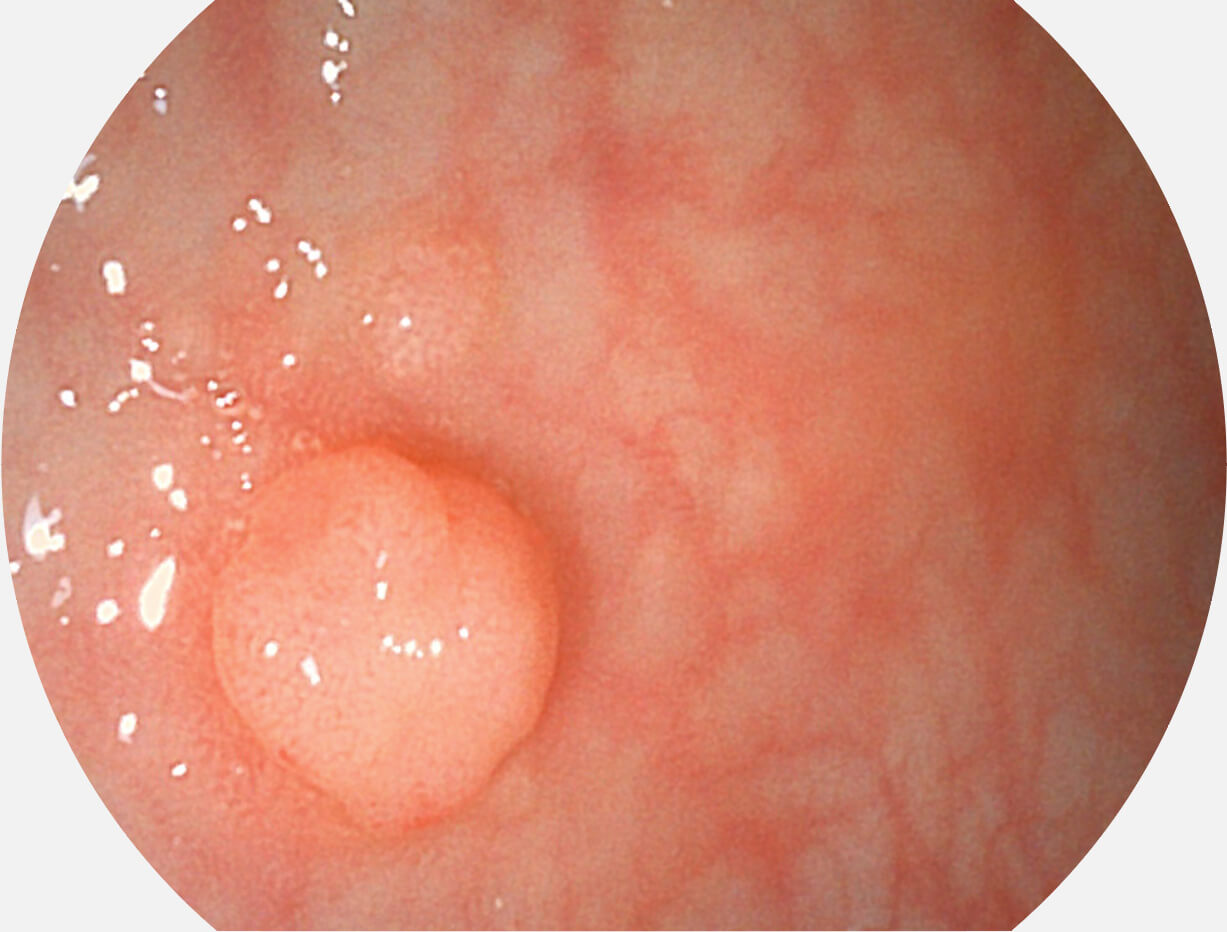

白光图像

VIST图像

强调浅层黏膜结构的同时,保证照明亮度和提升浅层微血管与中层血管颜色对比度,病变边界更清晰。